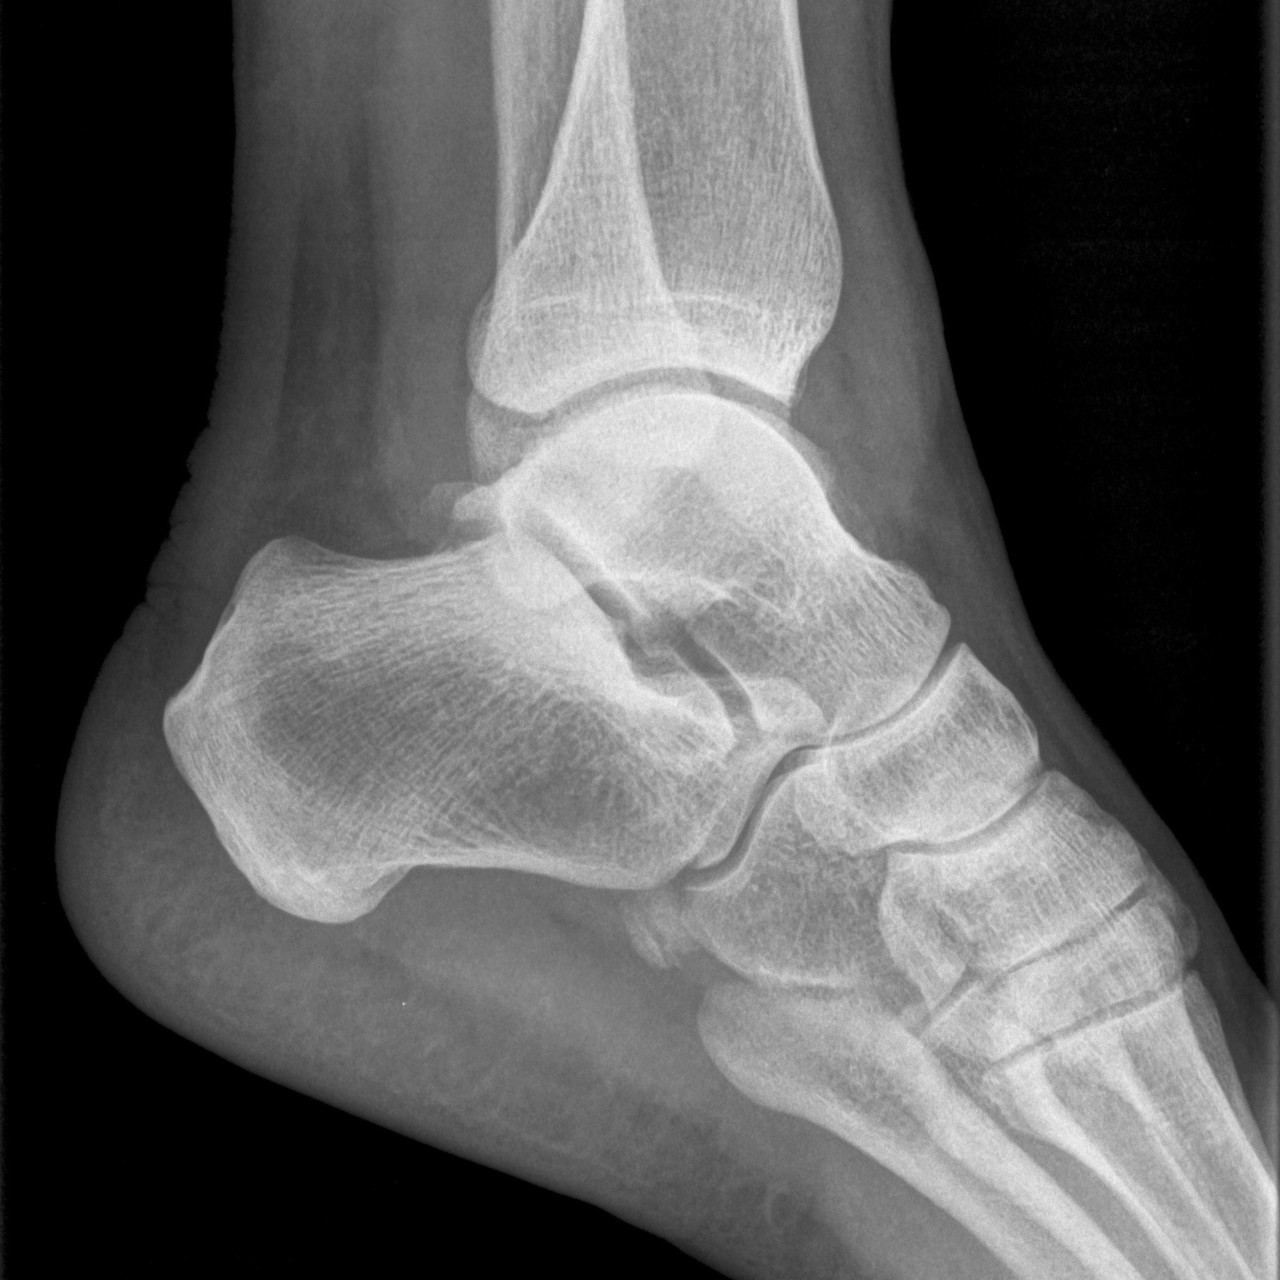

영상의학 검사

방사선 검사를 통해 해부학적 이상 소견 및 발의 정렬, 아치의 높이등을 확인하고 정밀 초음파로 인대 손상여부와 정도를 정확하게 파악하여야 올바른 치료의 방향을 결정할 수 있습니다.

영상의학검사